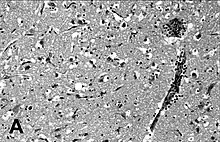

Encephalitis in the cerebral cortex of a harbor seal with PDV, stained with hematoxylin and eosin